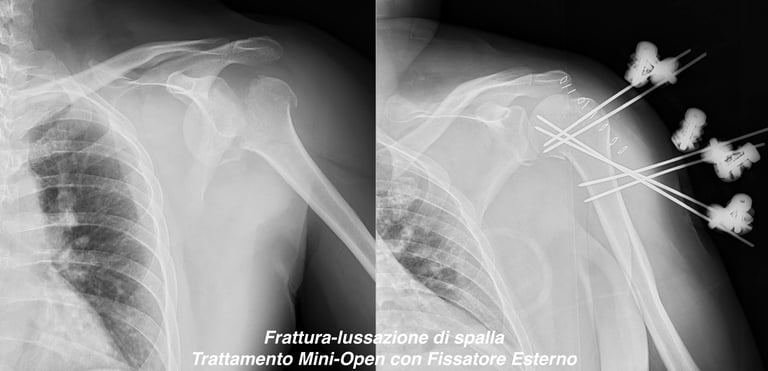

Patologia traumatica di spalla (scapola, clavicola e omero)

Gallery

Attività Chirurgica